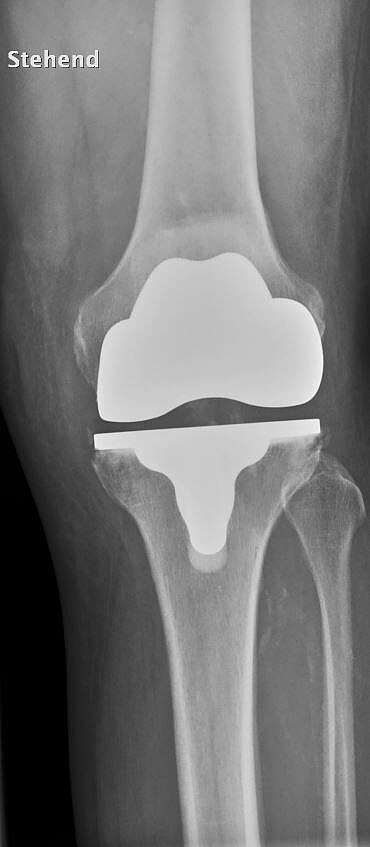

Die Behandlungen im Endoprothetik-Zentrum zielen darauf ab, das natürliche Gelenk eines Patienten zu bewahren. Nach einer umfassenden Diagnostik werden zunächst konservative Behandlungsmöglichkeiten ausgeschöpft. Zudem werden gelenkerhaltende Operationen angeboten. Bei fortgeschrittener Gelenkschädigung hilft oft nur ein künstlicher Gelenkersatz. Mit gewebeschonenden Implantationsverfahren, können individuelle maßgeschneiderte Implantate und Sonderprothesen eingesetzt werden.

Treten nach einer Implantation einer Prothese Beschwerden auf oder sind ursprüngliche Beschwerden nicht ausreichend behandelt, muss nach der Ursache gesucht werden. Körperliche Untersuchungen, Röntgenanalysen und bei Bedarf spezielle Zusatzuntersuchungen (diagnostische Punktion, MRT, etc.) liefern die Basis für die weiterführende Behandlung. Aufgrund unserer langjährigen Erfahrung kann in den meisten Fällen die Ursache analysiert und eine adäquate Therapie eingeleitet werden.